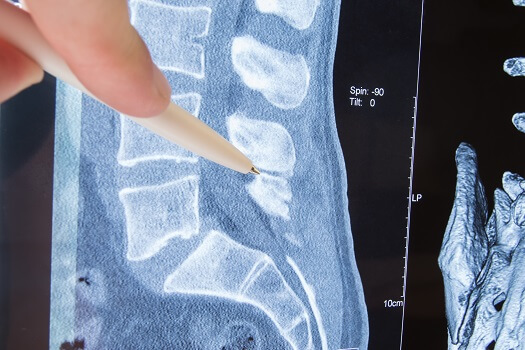

3 Imaging Tests Commonly Used to View the Spine

When you see a doctor about a spine-related problem, you’ll likely undergo a thorough physical examination and be asked to describe your symptoms and give some details about your history with back and/or neck pain. With some issues, such as […]